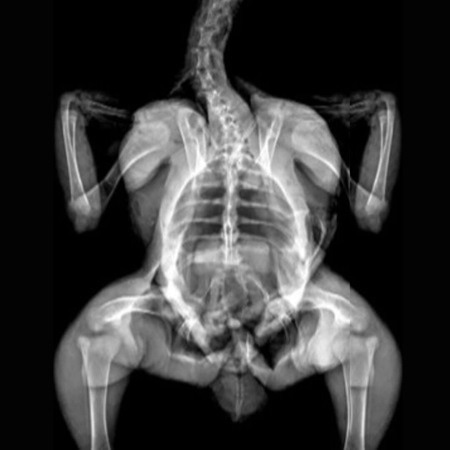

Image Credit: Kim, J. H., Lee, H., Kim, J. M., Lee, B.-J., Kim, I.-J., Pak, K., Jeon, Y. K., & Kim, K. (2022). Effect of oligonol, a lychee-derived polyphenol, on skeletal muscle in ovariectomized rats by regulating body composition, protein turnover, and mitochondrial quality signaling. Food Science & Nutrition, 10, 1184– 1194.